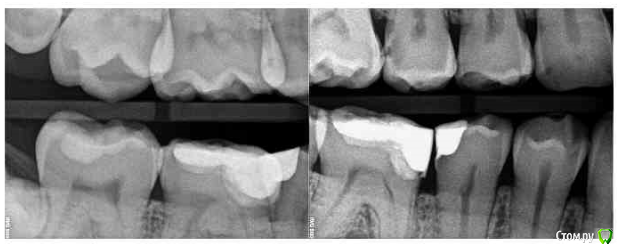

alex2016 Опубликовано 23 апреля, 2016 Поделиться Опубликовано 23 апреля, 2016 Добрый день, Сегодня был у стоматолога в профилактических целях. Т.к. нахожусь в США, то насчитали на ремонт 2600$ (учитывая страховку), т.к. 2600 тратить не сильно горю желанием хочу посоветоваться. Вопрос #1. В одном из зубов (его назвали №19 вроде как, снимок 1) врач обнаружил абсцесс. В этом зубе делали депульпирование и врач сказал, что депульпирование было сделано не до конца и на снимке это видно, т.е. они хотят заново вскрывать канал и заливать его (оба). К тому же он сказал, что в канале застрял кончик сверла (тут не уверен что это называется именно сверло) и его придётся доставать, возможно со стороны десны, если традиционным методом сделать это не получится. Абцесс он мне показал на снимке как небольшое затемнение на челюсти. Зуб не болит и кроме того, что между ним застряёт еда и он сам выглядит не презентабельно ничем не мешает, врач предлагает ставить коронку. Насчёт коронки возражений нету, т.к. еда застряёт и зуб выглядит не презентабельно, хотя в глаза это не бросается т.к. это моляр, а вот насчёт абсцесса я бы хотел уточнить здесь и получить второе мнение. Вопрос #2. Доктор предлагает поставить коронку на зубе #30, картинка #2. Хотя на зубе и достаточно большая пломба, он не выглядит не презентабельно и абсолютно не беспокоит, конечно, он выглядит чуть хуже обычного зуба, но гораздо лучше зуба #1. Сам я склоняюсь к тому, что пока с этим зубом делать ничег не нужно, но второе мнение хотелось бы всё-таки выслушать. Вопрос #3. Доктор предлагает удалить верхние зубы мудрости, т.к. они оказывают давление на дёсны или ещё куда-то там. Здесь я склоняюсь к тому, что он может быть прав насчёт верхнего зуба, потому что у меня там периодически застряёт еда между десной и самим зубом и вызывает неприятные ощущения, правый верхний зуб мудрости абсолютно никаких негативных ощущений не вызывает. Есть ли возможность избавиться от застрявания еды между зубом и десной (это происходит сзади-справа) без удаления зуба? Можно ли удалять один зуб мудрости, а не оба? Вопрос #4. У меня не правильный прикус из-за которого сточились передние верхние зубы, доктор предлагает удалить два верхних зуба, которые идут за клыками, подтянуть верхние передние зубы вперёд и поставить на них коронки, чтобы вернуть хороший прикус и эстетику (сейчас при закрытом рте расстояние между передними зубами верхней челюсти и нижней примерно в 1см). Вся эта процедура займёт кучу времени, т.к. придётся ставить брекет систему и удалять зубы. В клинике в Киеве мне тоже предлагали такой вариант. Зубы хочу сделать, чтобы улыбка стала красивее, поэтому вопросы: А. Обязательно ли удалять 2 зуба для этой процедуры?Б. Если удалить два верхних зуба мудрости, не отодвинутся ли зубы назад сами по себе?В. Хороший ли вариант ставить коронки на абсолютно здоровые, но немного сточенные зубы дли улучшения эстетики? Возможно зубы можно просто нарастить?Г. Не повлияет ли удаление двух зубов на положение верхней губы? При закрытом рте отклонений в прикусе особо не заметно. Благодарю за ответы. Ссылка на комментарий

DmitrySH Опубликовано 23 апреля, 2016 Поделиться Опубликовано 23 апреля, 2016 вопрос 2.Может быть не коронку, но керамический оверлей очень кстати, и вкладку или пломбу на 5ый зуб перед ним и 5ый над ним. Ссылка на комментарий

alex2016 Опубликовано 23 апреля, 2016 Автор Поделиться Опубликовано 23 апреля, 2016 (изменено) Вопрос 1.Да, ревизия каналов нужна, коронка нужна, инструмента не увидел на снимке, самое интересное срезано.. нужен снимок еще как минимум 5 мм ниже.Вот сделал скриншот с другой фотографии. Качество какое есть, если нужно могу спросить нет ли у них качества получше, такое впечатление что отсканировали в самом плохом качестве, т.к. то что они мне показывали выглядело более детализировано. вопрос 2.Может быть не коронку, но керамический оверлей очень кстати, и вкладку или пломбу на 5ый зуб перед ним и 5ый над ним.Благодарю. Доктор, почему-то не упоминал об этой возможности, рассказывал только про импланты и коронки. Уточню насчёт этого. 3 вопрос, скорее всего да, но не по снимку об этом рассуждатьДа в плане того, что можно удалять только один зуб, или то, что можно избавиться от проблемы без удаления зуба? Зуб не болит абсолютно и я даже не знал о том, что это зуб мудрости, просто когда я ем орехи или морковку и они попадают между десной и зубом, то десна воспаляется и вызывает неприятные ощущения, вот сейчас абсолютно нормально и зуб не достаёт совсем, но когда доктор смотрел этот зуб я отчётливо понял, что это именно то место, потому что он его немного зацепил своим прибором, т.е. какая-то проблема там есть, но неужели такая мелочь решается только методом удаления зуба? Изменено 23 апреля, 2016 пользователем alex2016 Ссылка на комментарий